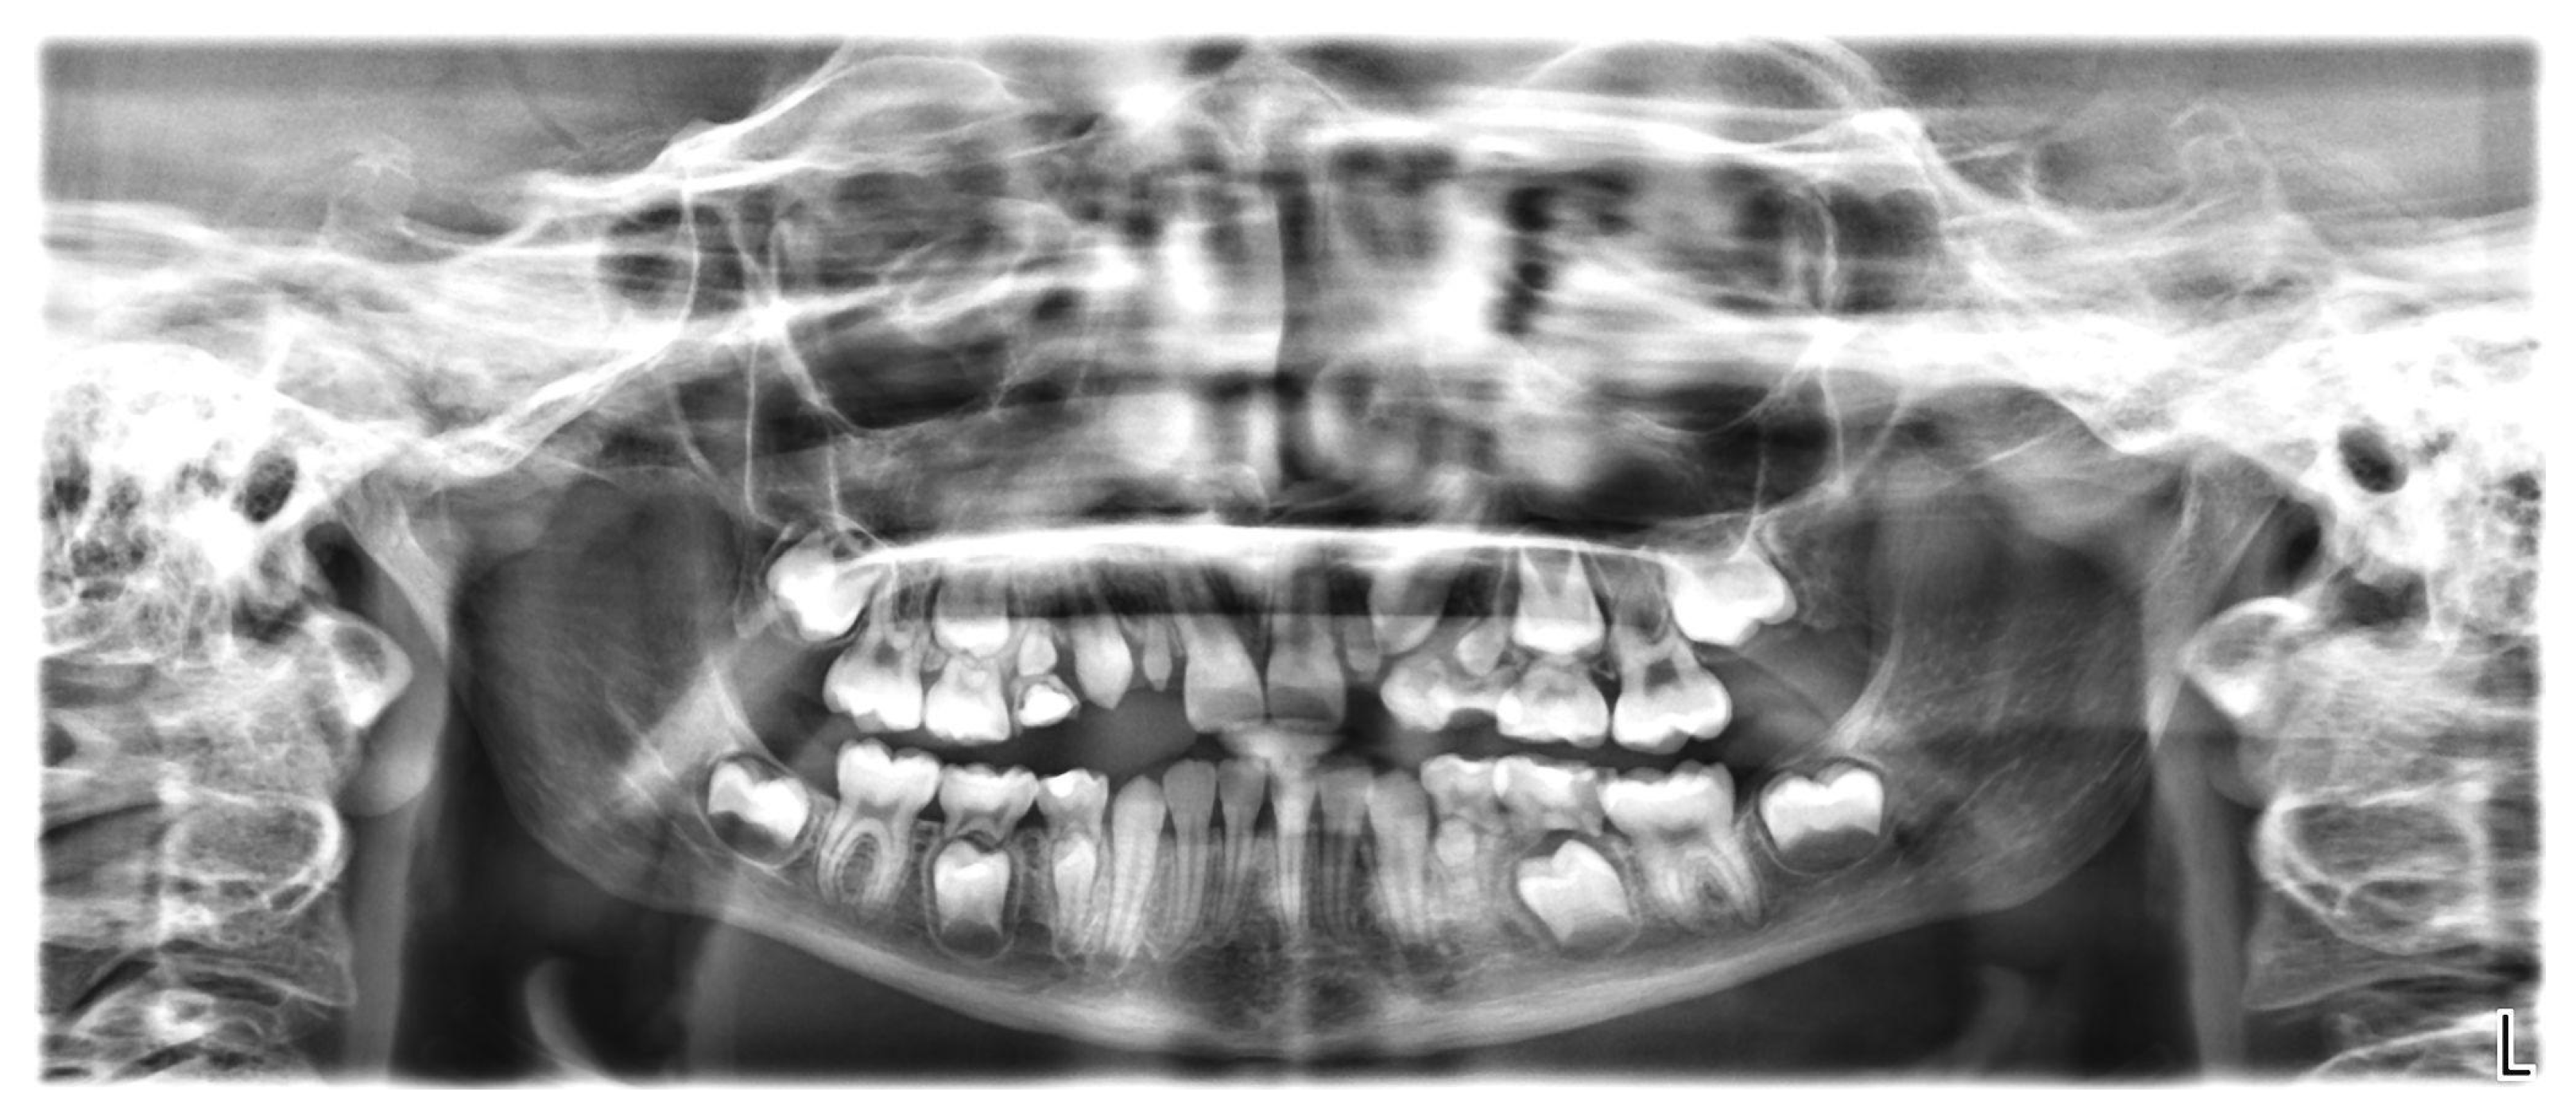

2.4. Radiological Examination

The orthopantomogram showed the presence of all permanent teeth at varying stages of development and eruption, but the microdontia of six teeth (Figure 5). In particular, the crowns of all first premolars (both maxillary and mandibular) and maxillary permanent lateral incisors were reduced in size. In the family history, microdontia was not present.

Figure 5.

Orthopantomogram of a 9-year-old girl showing reduced size of teeth 14, 12, 22, 24, 34, and 44.

The root dimensions appeared to be normally formed (Figure 5).